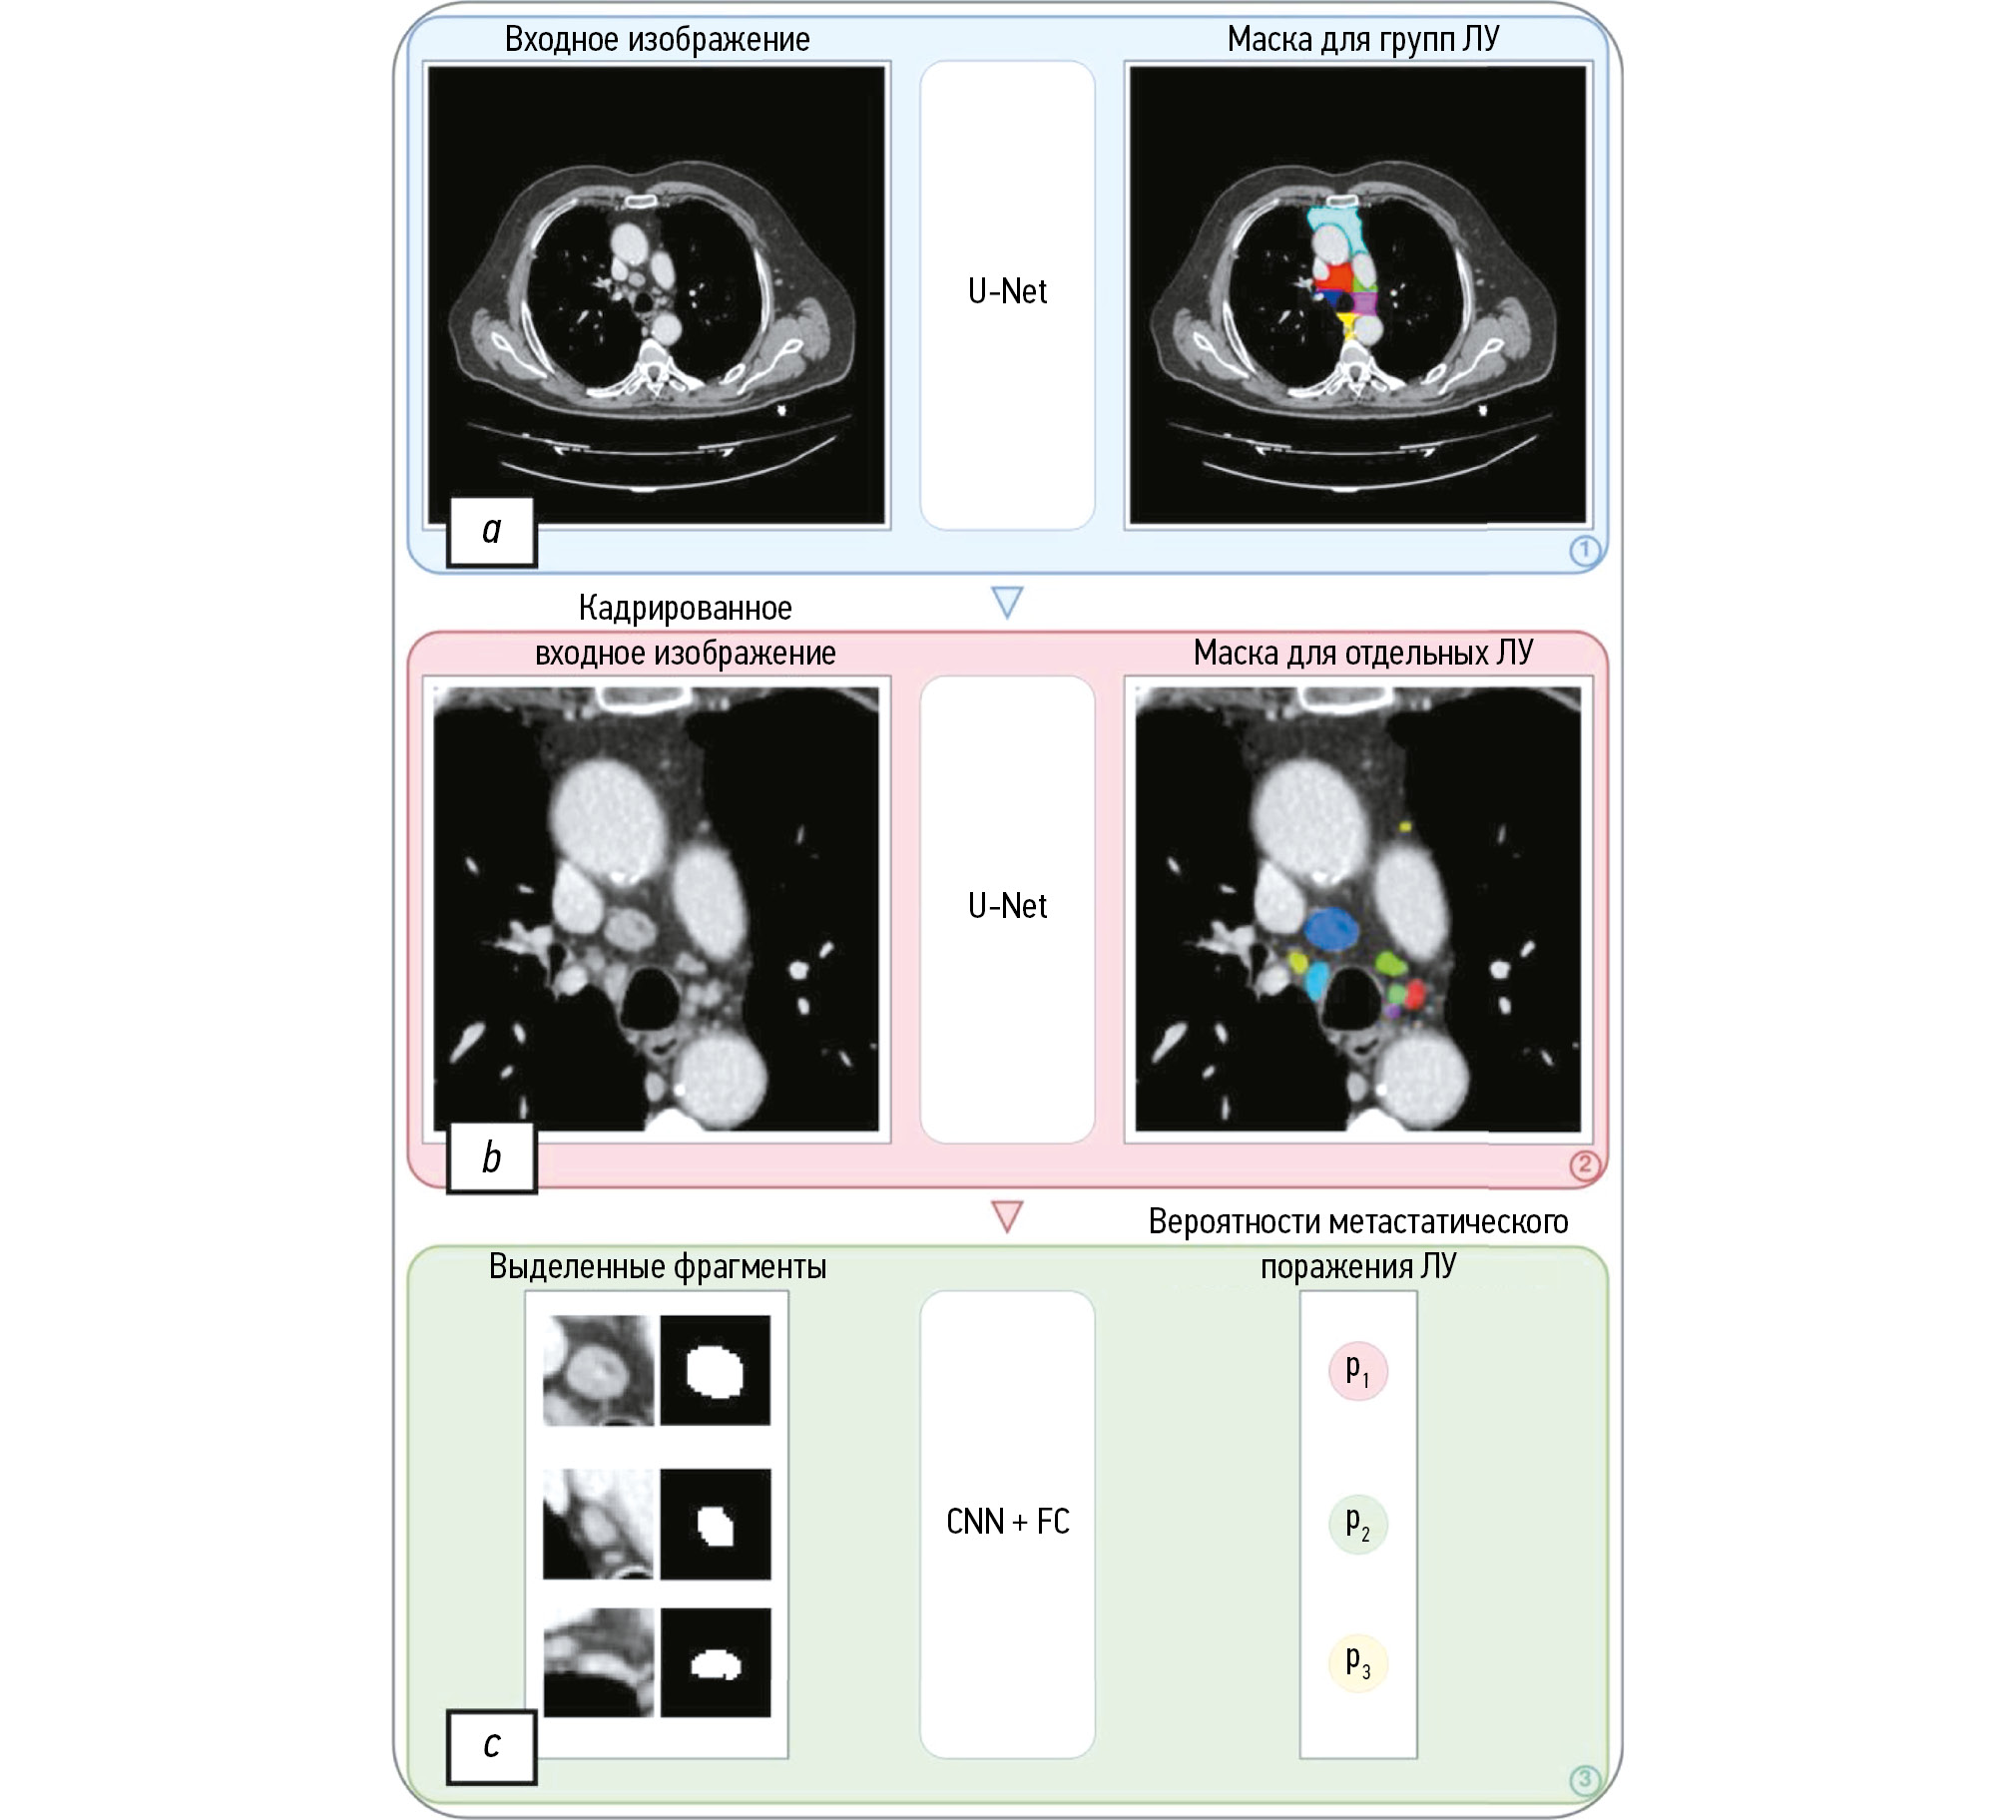

The proposed algorithm for lymph node segmentation and metastasis classification involves a three-stage process:

First stage: identification of lymph node groups and mediastinum segmentation in the region of interest are essential for determining the extent of regional lymph node involvement [12];

Second stage: cropping the input image and segmentation of all visible lymph nodes using a bounding box for the mediastinum;

Third stage: analyzing all identified lymph nodes using a feedforward network to determine the probability of metastasis.

The results provide information on lymph node involvement in specific groups, enabling evaluation of the degree of involvement based on the tumor site. Subsection 3.1 addresses the segmentation of lymph node groups; subsection 3.2 examines the segmentation of individual lymph nodes; and subsection 3.3 discusses the classification of lymph node involvement.

This study used a two-component U-Net model for the 3D segmentation of lymph node groups (Fig. 1) [41]. While the first component distinguished between the mediastinum and the background, the second component classified each voxel within the mediastinal mask to a specific lymph node group. Advanced deep learning technologies, such as ResBlocks, batch normalization, and the ReLU activation function, were used after each convolution, except for the data output [42–44].

Fig. 1. Three-stage algorithm for lymph node segmentation and metastasis classification: a, segmentation of lymph node groups; b, image coding based on the bounding box and processing using a second network; c, marking each identified lymph node, applying the respective mask, and assessment through a feedforward network. LN, lymph node.

To preserve computing resources during the second stage, the region of interest should be marked employing the bounding box for the mediastinum obtained in the first stage. If the size in the axial view exceeds 128 pixels, filling is used to achieve the minimal size of 128 pixels.

During this stage, the architecture was comparable to the one used for the segmentation of the lymph node groups. However, it offers a pooled binary data output for a lymph node segmentation prognostic map with more channels and fewer levels (see Fig. 1). This design is adapted to individual lymph nodes that are substantially smaller than the groups; thus, a large receptive field is not required. The design provides for additional characteristics that boost segmentation accuracy.

Classification of lymph node involvement

In weak supervision, a metastasis label is assigned to a lymph node group, and the probability of metastasis for each lymph node is predicted. Lymph nodes are marked on 32 × 32 image fragments for study purposes. They are merged with respective masks to combine all identified objects in a single dataset. Data is processed using convolutional neural networks with a five-level ResNet architecture, followed by max-pooling to minimize spatial dimensions [42]. During the final stage, data is analyzed using the sigmoid and fully connected layers to assess the probability of metastasis for each lymph node.

This is further complicated by the fact that in contrast to benign lymph nodes, metastases might be present or absent in malignant lymph node groups. Thus, a benign lymph node group has no affected lymph nodes, whereas a malignant group must have at least one. To satisfy this requirement, a unique loss function is used. The binary cross-entropy loss function was used for training to assess the probability of metastasis in all benign group lymph nodes. For lymph nodes with metastasis, training is only performed if the prognostic data indicates that is all lymph nodes in this region are benign (see Fig. 1). This method has both advantages and disadvantages.